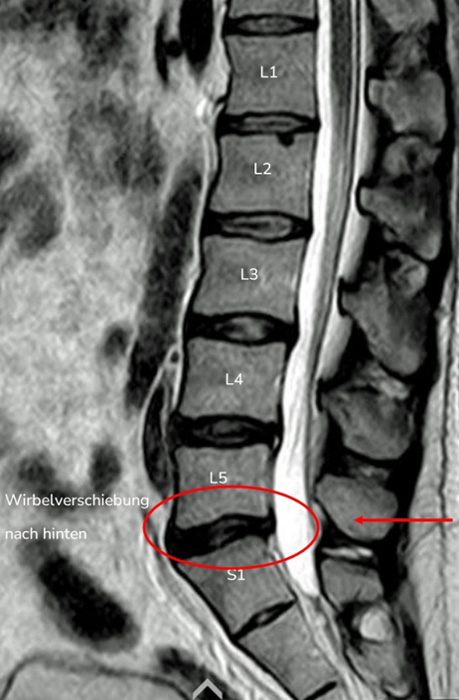

2. Beispiel – Wirbelverschiebung nach hinten

Auch bei dieser Aufnahme kann man Ähnlichkeiten zwischen der MRT-Aufnahme und der Konturdarstellung der Medi Mouse erkennen.

Bei dieser Wirbelsäulenform ist die normale Lordose der Lendenwirbelsäule nicht vorhanden, das Gegenteil ist der Fall, die Kyphose ist bis zum Kreuzbein verlängert.

Dies als Folge einer Rückverlagerung des Oberkörpers, was dazu führt, dass das eine Knicktendenz nach hinten entsteht und die Wirbelverschiebung nach hinten begünstigt.